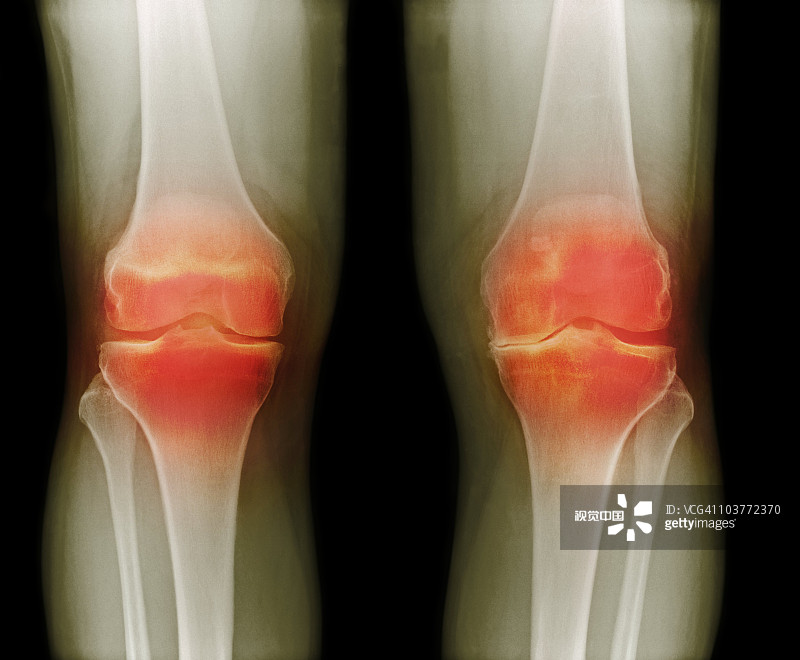

適應癥:膝骨關(guān)節炎

貴醫附院 | 人臍帶間充質(zhì)干細胞治療膝骨關(guān)節炎患者的1期臨床試驗

- 2.依據參考中華醫學(xué)會(huì )骨科學(xué)分會(huì )關(guān)節外科學(xué)組制定的“骨關(guān)節炎診療指南(2018年版)”,明確診斷為膝骨關(guān)節炎(KOA)